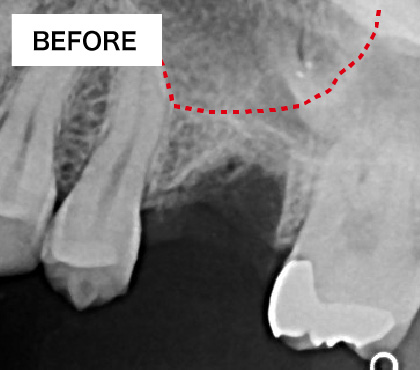

骨が少ない場合①

歯槽骨が吸収し、上顎洞が下がっています。このままではインプラントが突き抜けてしまうためインプラントはできません。

骨が少ない場合②

インプラントを支えるための歯槽骨が十分でないためインプラントはできません。

BEFORE・AFTER